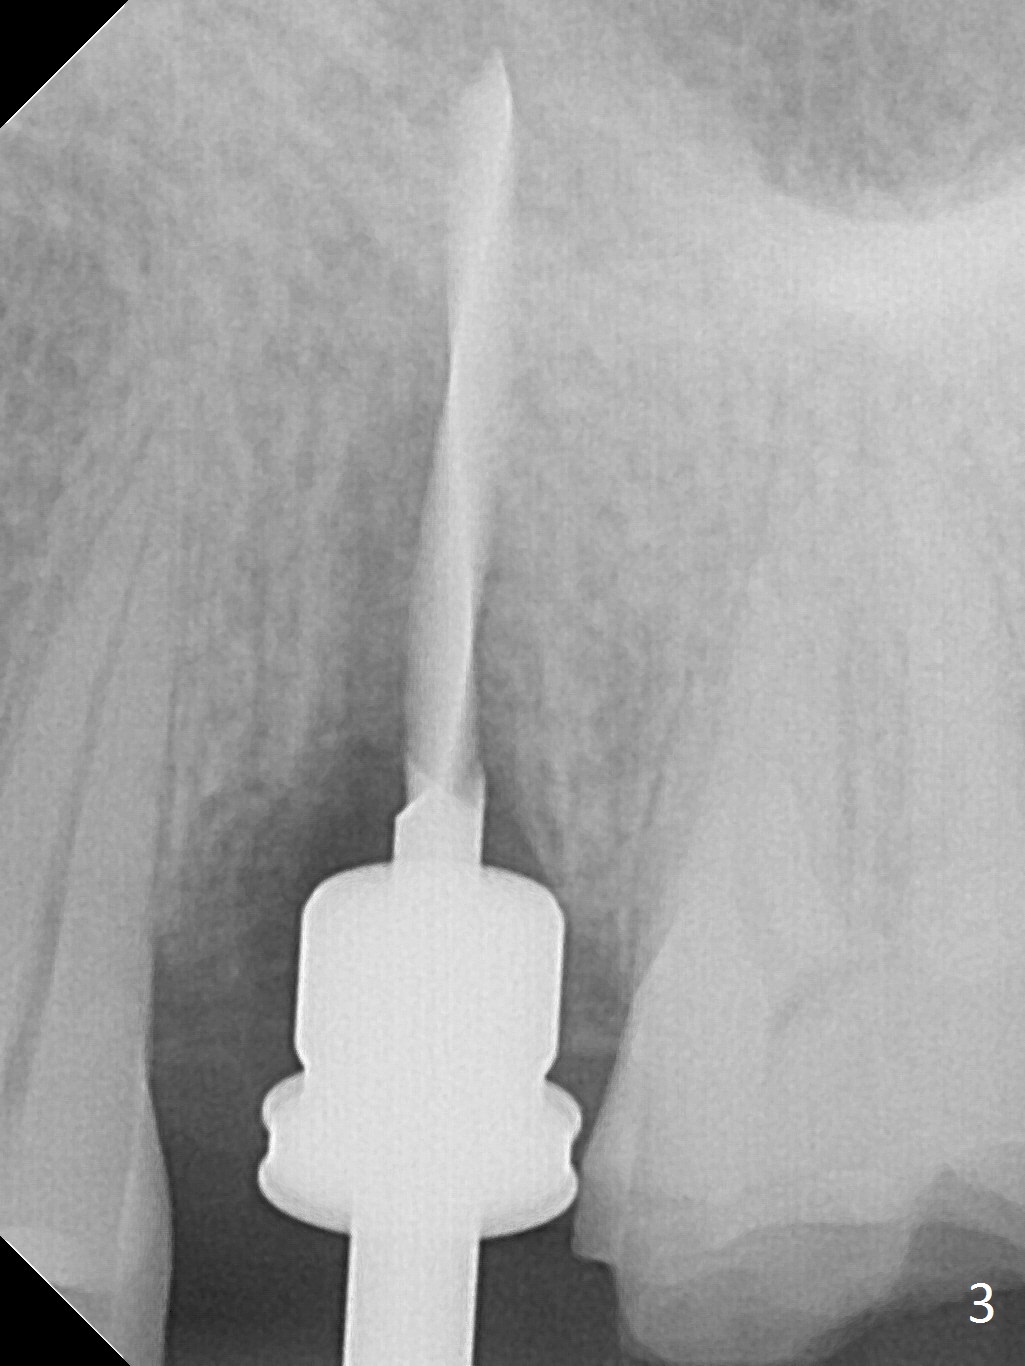

The buccal gingiva over the tooth #13 (Fig.1 white *) with crack (Fig.2 (mesial view of the extracted tooth)) is erythematous with deep buccal (B) pockets, which do not appear to extend the level of exostosis of the neighboring teeth (Fig.1 black *), i.e., coronal to the apical end of the crack with granulation tissue (Fig.2 *). Osteotomy is initiated with a 1.6 mm drill in the palatal aspect of the socket (Fig.3) so that an implant will be placed palatal (Fig.8,11) and there is enough buccal gap for bone graft (Fig.8 *). After withdrawal of 3.3 mm Magic Drill (trephine bur), the osteotomy (Fig.4 O) plug (red outline) is intentionally left in situ. When a 4x11 mm dummy implant is placed (Fig.5 (green outline), 6), the plug is compressed (Fig.5). With placement of a definitive implant (4.5x13 mm, Fig.7 (green), 9), the plug as well as the sinus floor (Fig.4 SF) is lifted (Fig.7 red curved line), 9 (arrowheads)). In brief the autogenous bone is used for sinus lift. There is no intra- or post-op nasal hemorrhage. With a small piece of gauze (Fig.8 G) in the implant well, allograft is placed in the buccal (mainly) and palatal gaps until the level of the implant plateau. Then a 4.5x4(3) mm abutment is placed (Fig.9-10 A). Next another piece of gauze is placed in the space corresponding to the abutment cuff (Fig.11 G) for fabrication of an immediate provisional (Fig.12 P). More bone graft is placed in the soft tissue zone (dual zone technique) after gauze removal and before provisional seating. With dual zone bone graft technique and provisional support, the soft tissue atrophy should be expected to be minimal (Fig.12 *). The zone of exostosis (more coronal) should be much less, since the bone density in the zone is high.